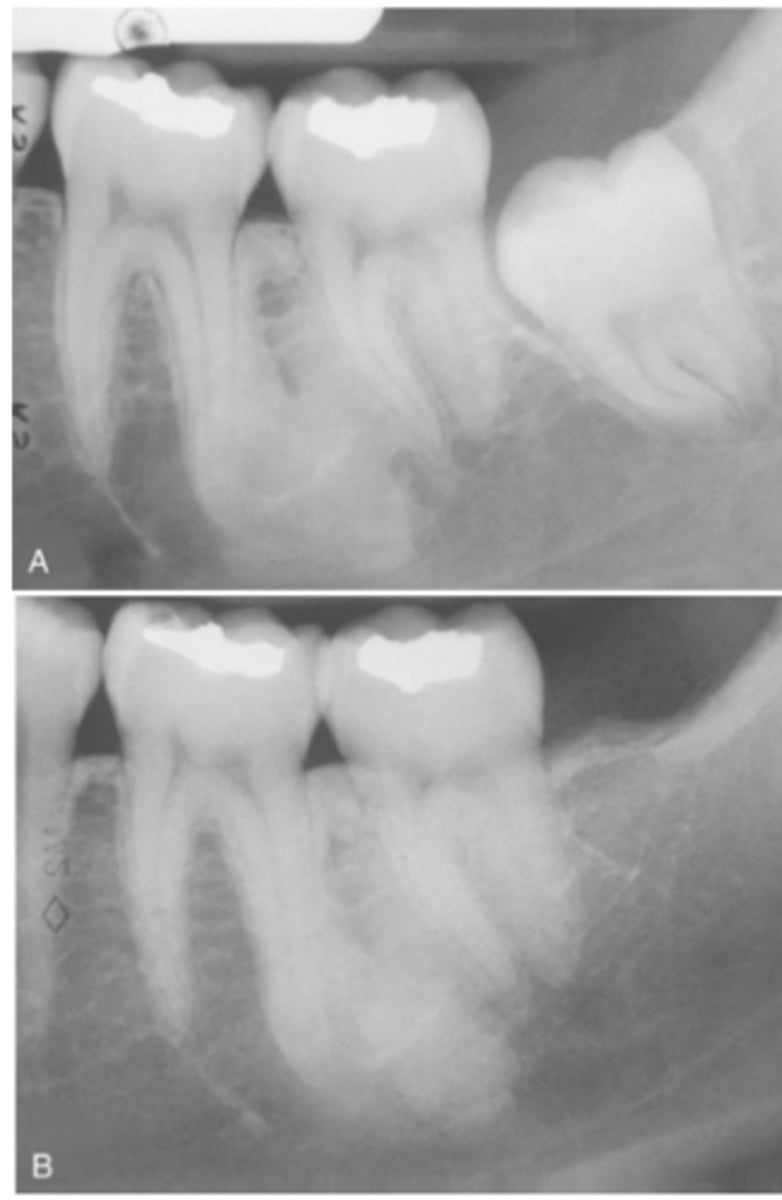

What do radiographic signs show in Idiopathic Osteosclerosis

Well-defined radiopacity

Most are associated to a root apex

If there is signs of cortical expansion in Idiopathic Osteosclerosis what needs to be taken?

biopsy

What is the treatment for Idiopathic Osteosclerosis

Follow-up with radiographs if discovered during adolescence